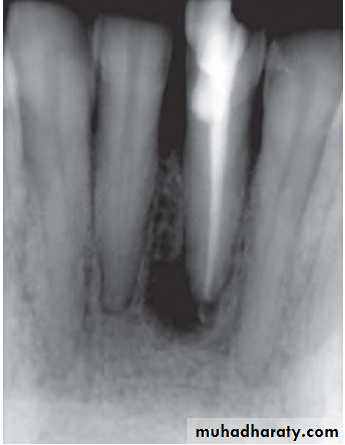

• Clinically:“Pink Tooth” appearance• Radiographic changes:

– Radiolucent enlargement of pulp canal

– Original root canal outline distorted

– Bone changes are seen only when root perforation into periodontal ligament takes place.